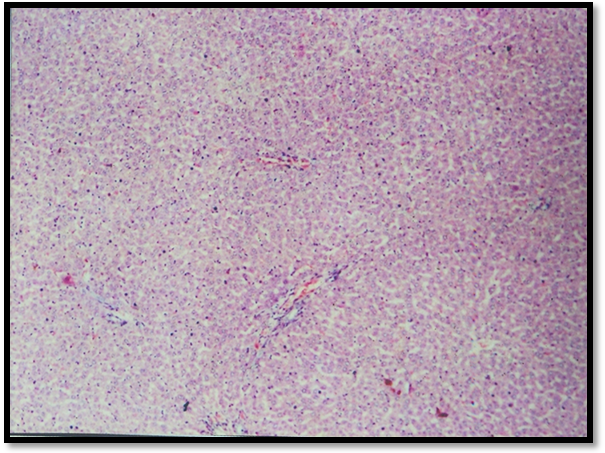

Histopathological observations

Histopathology of normal rat liver revealed prominent central view, normal arrangement of hepatic cells (Fig. 7). Microscopic examination of CCl4 treated liver section shows necrosis and fatty degeneration (Fig. 8). Liver section treated from Silymarin protected the structural integrity of hepatocyte cell membrane and recovery of hepatocyte cells (Fig. 9). Scopoletin treated group showed maximum recovery of hepatocytes, no fatty degeneration and necrosis and exhibited significant protection against CCl4 induced liver toxicity in rats (Fig. 10).

Photomicrographs of liver tissues of different groups of Albino rats

Fig. 7: Normal group